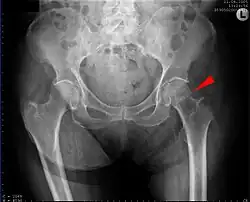

![]() | |

| Intertrochanteric hip fracture in a 17-year-old male | |